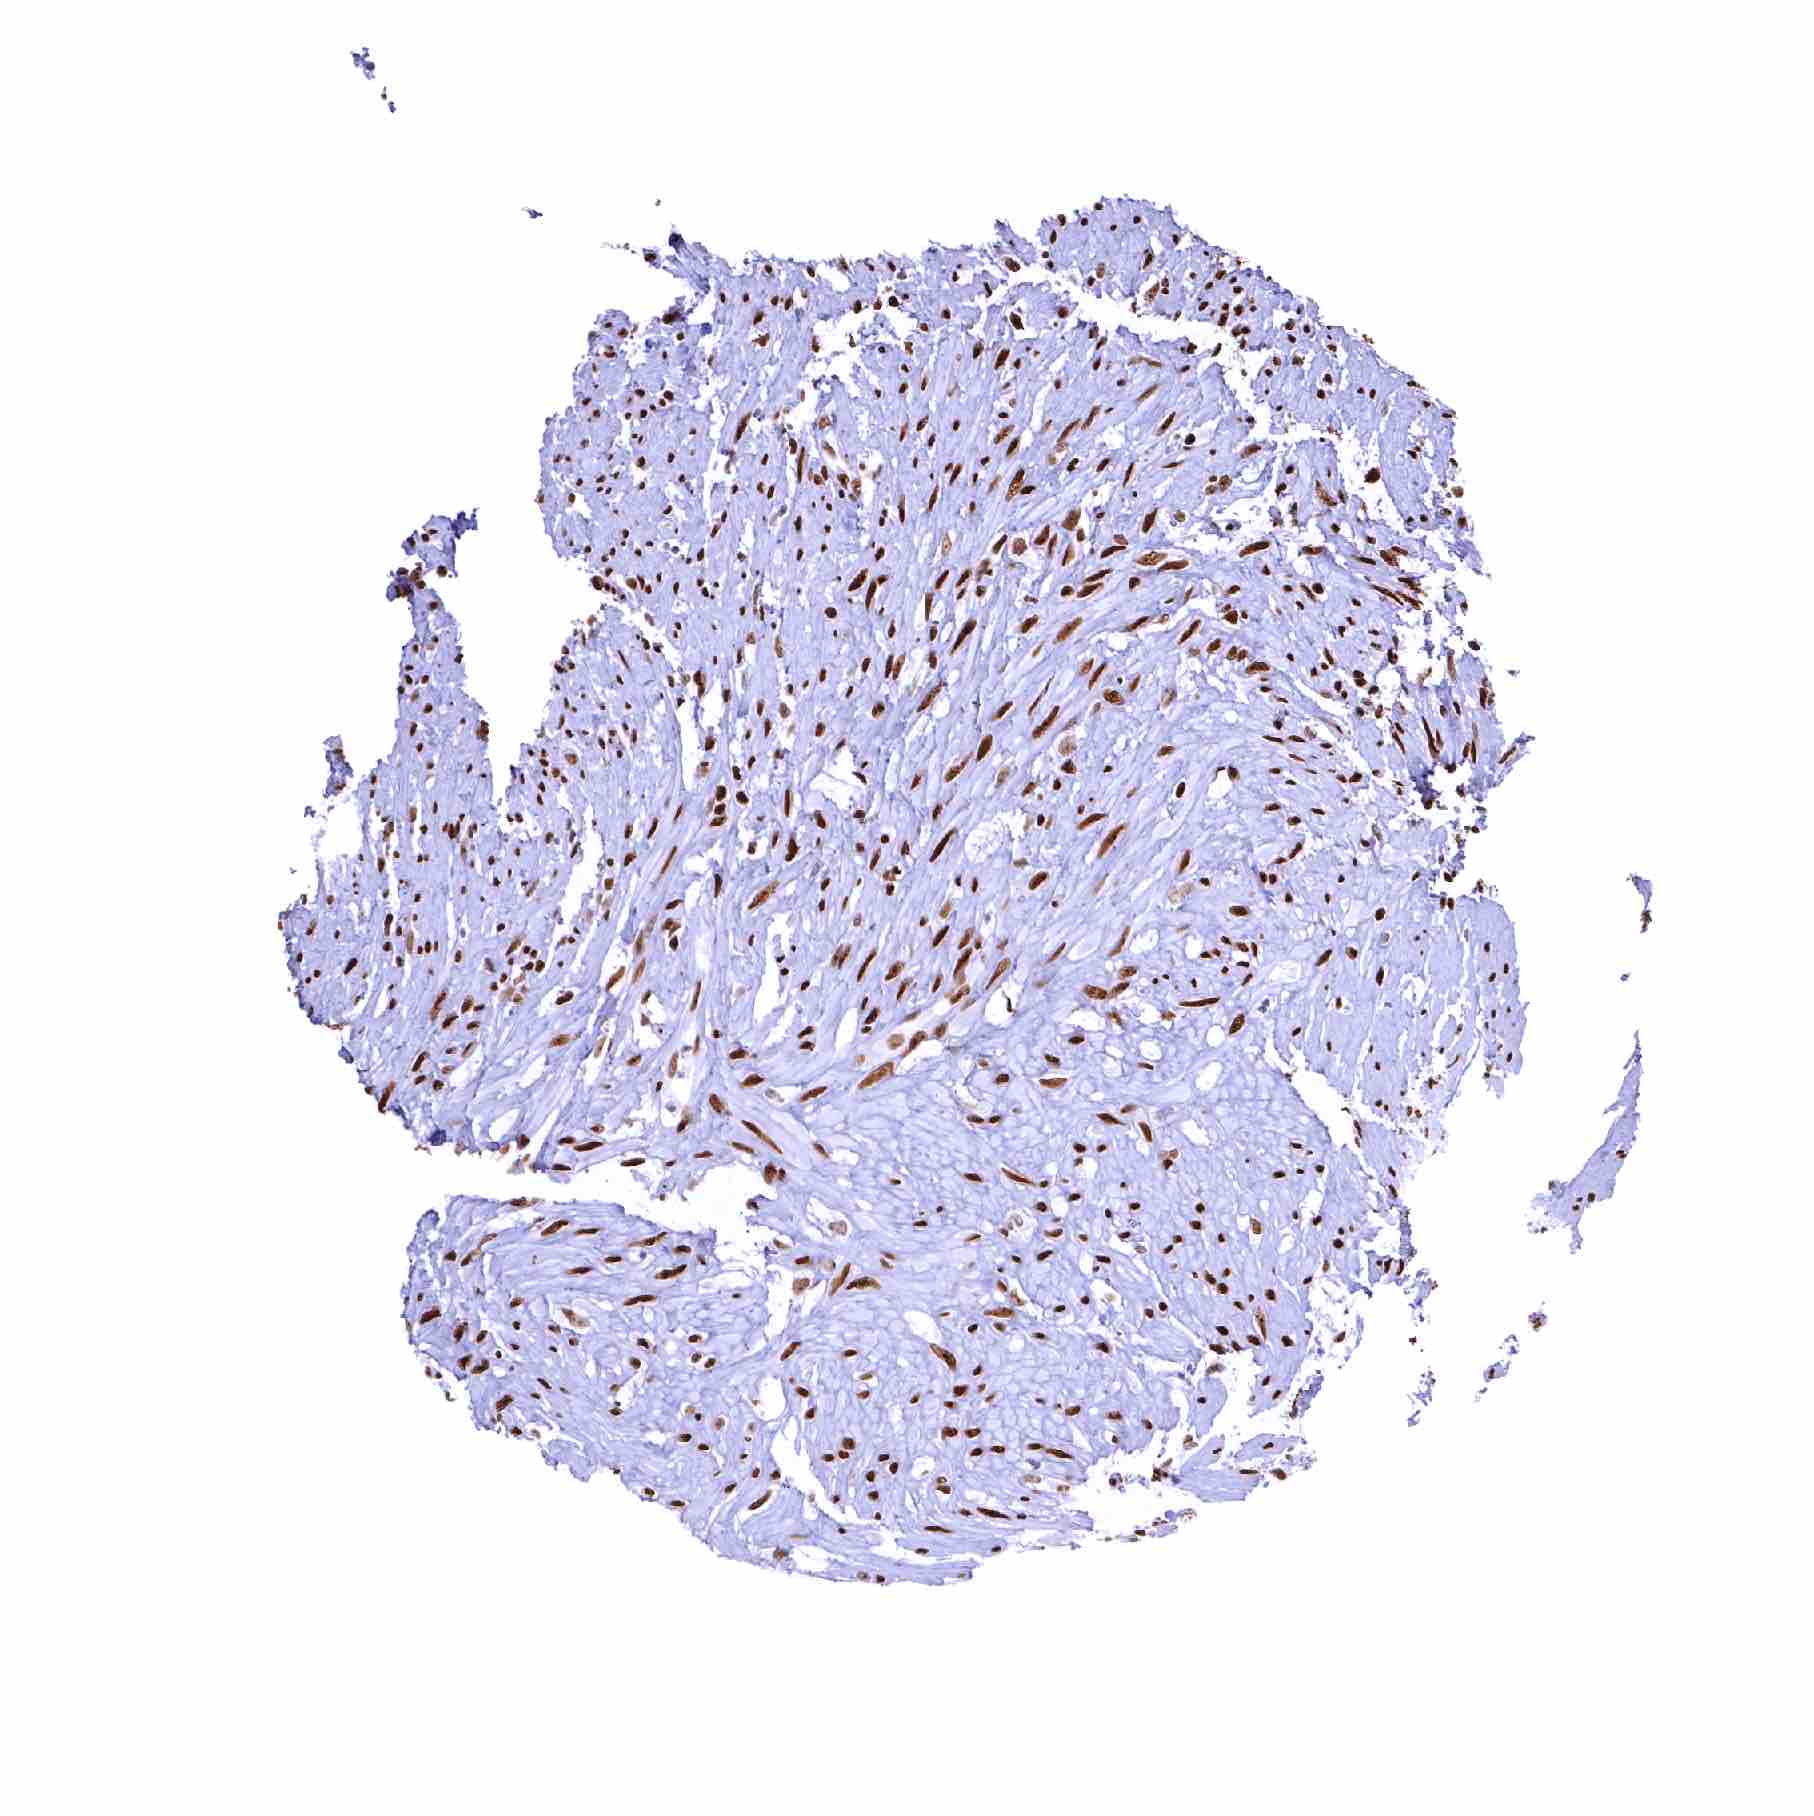

Urinary bladder, muscular wall